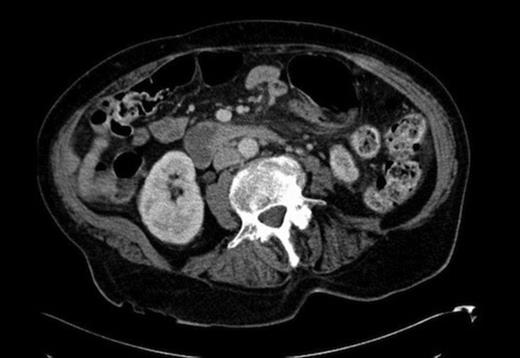

The following morning, she underwent Helical Computed Tomography (CT) of her abdomen and pelvis. This revealed her caecal pole to be situated in the left upper quadrant, with evidence of fat stranding between the caecum and pancreas(fig 2). The appendix was not visualised. The liver, spleen, stomach and pancreas all had normal CT appearances and were in their expected, anatomical locations. Other findings were cystic duct clips from a previous cholecsytectomy and intra-hepatic biliary duct dilatation (max diameter of the CBD 1.2cm). There was also an atrophic left kidney but no evidence of lymphadenopathy, (some of the images were degraded by artefact from a DHS fixation of the left hip), and no evidence of bowel obstruction or appendicolith.

CT showing the caecal pole to be situated in the left upper quadrant, with evidence of fat stranding between the caecum and pancreas